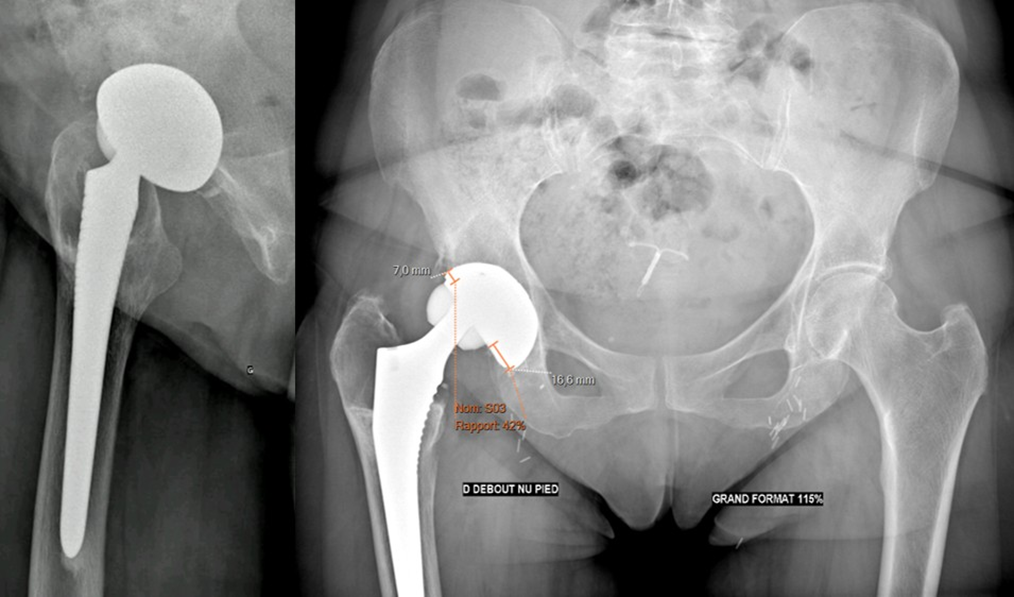

Given the disabling pain and probable implant wear, a one-stage acetabular component and femoral head revision was indicated and performed in July 2024.

Revision surgery took place 11 years after the index procedure under general anesthesia, in left lateral decubitus. The initial posterolateral approach was reused. Intraoperatively, a grayish tissue adherent to the capsule was noted, but no granuloma. A millimetric ceramic fragment was found at the expense of the acetabular liner. Both the ceramic femoral

head and acetabular liner were deformed and asymmetric (Figure 4). The metal-back shell was removed without significant bone loss. After removal of the femoral head, the femoral stem showed no signs of wear or loosening and was left in place. A 61 mm diameter HYPE acetabular cup (SERF®) with a HYPE ceramic liner (SERF®) for 36 mm head was implanted after failure to obtain satisfactory stability with an Anexys cup (MATHYS®). A Biolox Option revision ceramic femoral head 36/+5 mm (SERF®) was implanted on the original femoral stem.

Figure 4. Retrieved worn implants (a)* Acetabular components and ceramic femoral head ; (b)* Wear and loss of sphericity of the ceramic femoral head ; (c)* Ceramic femoral head in situ ; (d)* Wear of the ceramic liner with exposure of the metal-back.

Full weight-bearing was allowed immediately postoperatively. At discharge, five days after surgery, the patient reported no squeaking, was pain-free, and was ambulating independently with a single crutch. Postoperative radiographs are shown in Figure 5.